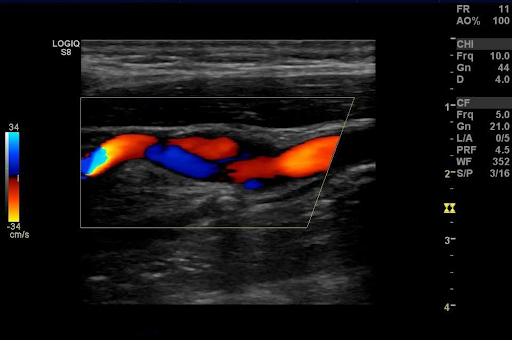

Диагностика и лечение сосудистых патологий, в частности, атеросклероза – вопросы, которые всегда актуальны. Одним из широко распространенных методов исследования сосудов шеи и кровотока в них является дуплексное сканирование брахиоцефальных артерий (БЦА). Этот способ представляет собой ультразвуковую диагностику магистральных кровеносных сосудов на шее, отвечающих за кровоснабжение головного мозга. Брахиоцефальные сосуды отходят от аорты, разветвляясь на более мелкие сосуды, часть из которых отвечает за кровообращение в руках, а другая часть поднимается к голове. Во время ультразвукового исследования визуализируются общие, наружные, внутренние сонные и позвоночные артерии. Посредством цветового допплеровского сканирования исследуется гемодинамика.

Дуплексное сканирование проводится в кабинете УЗ-диагностики. Пока пациент лежит на кушетке, специалист использует датчики разной частоты и проводит устройством по поверхности шеи - с левой, затем с правой стороны. В то же время изображение БЦА транслируется на мониторе. Оно позволяет оценить диаметр сосудов, состояние их стенок, а также проходимость и показатели кровотока. Если необходимо отследить состояние некоторых функциональных проб, пациента просят изменить положение головы. В целом, сканирование длится в пределах 20-40 минут. По завершении процедуры, врач фиксирует все полученные данные и составляет заключение с рекомендациями, а также указывает сроки повторного исследования.

Дуплексное сканирование позволяет оценить состояние крупных, периферических сосудов и мелких подкожных капилляров, а также распределение крови в просвете русла. Заметно любое патологическое отклонение от нормы. Зрительная оценка имеющихся изменений внутри просвета кровеносного сосуда позволяет диагностировать заболевание на раннем этапе. Выявление патологического процесса возможно на любом участке сосудистого бассейна.